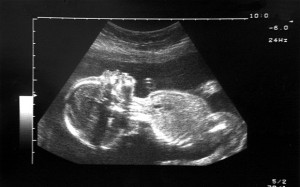

Politicians and Columnists concerned that Abortions of Fetuses with Clefts Constitute “Eugenics.”

Late-term abortions of fetuses with clefts Some Members of Parliament in the UK have called for a review of abortion laws since recent data show many more mothers than realized ask that their cleft fetuses be aborted. According to a committee of MPs and peers, evidence suggests "many pregnancies are being terminated up until full term simply because of cosmetic flaws." Mothers and doctors are engaging in "discrimination" according to some. I'd second this: sounds like "facial … [Read more...]